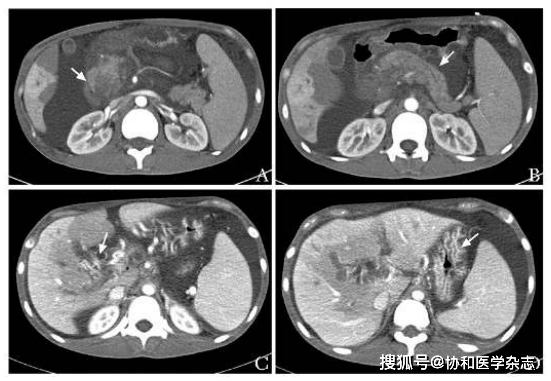

腹部CT平扫+胰腺CT薄层扫描示胰头增大 , 密度不均匀 , 周围多发增大淋巴结 , 肝内外胆管扩张 , 脾大 , 腹膜后似见肿大淋巴结(图1) 。

图1 腹部CT平扫+胰腺CT薄层扫描示胰头增大 , 密度不均匀(箭头 , 2019年4月9日)A.冠状面;B.横断面

腹盆增强CT+胰腺CT薄层扫描:腹腔新见大量积液;肝实质内片状门静脉期强化减低影;肝S6 段结节斑片样强化减低灶 , 占位性病变不除外;与4月9日CT相比 , 胰头增大 , 密度强化不均匀 , 较前加重;胰管轻度扩张;新片示门静脉主干及肝内分支充盈不清 , 门静脉海绵样改变 , 食管胃底及门静脉其它属支多发静脉曲张(图2);新见肝门区片状低密度低灌注;肝内外胆管略扩张 , 增强后胆总管下段被异常强化血管团包裹、狭窄;脾大;腹膜后似见肿大淋巴结 。

图2 腹盆增强CT+胰腺CT薄层扫描图像(2019年4月29日)A.胰头增大 , 密度强化不均匀 , 较前加重(箭头);B.胰